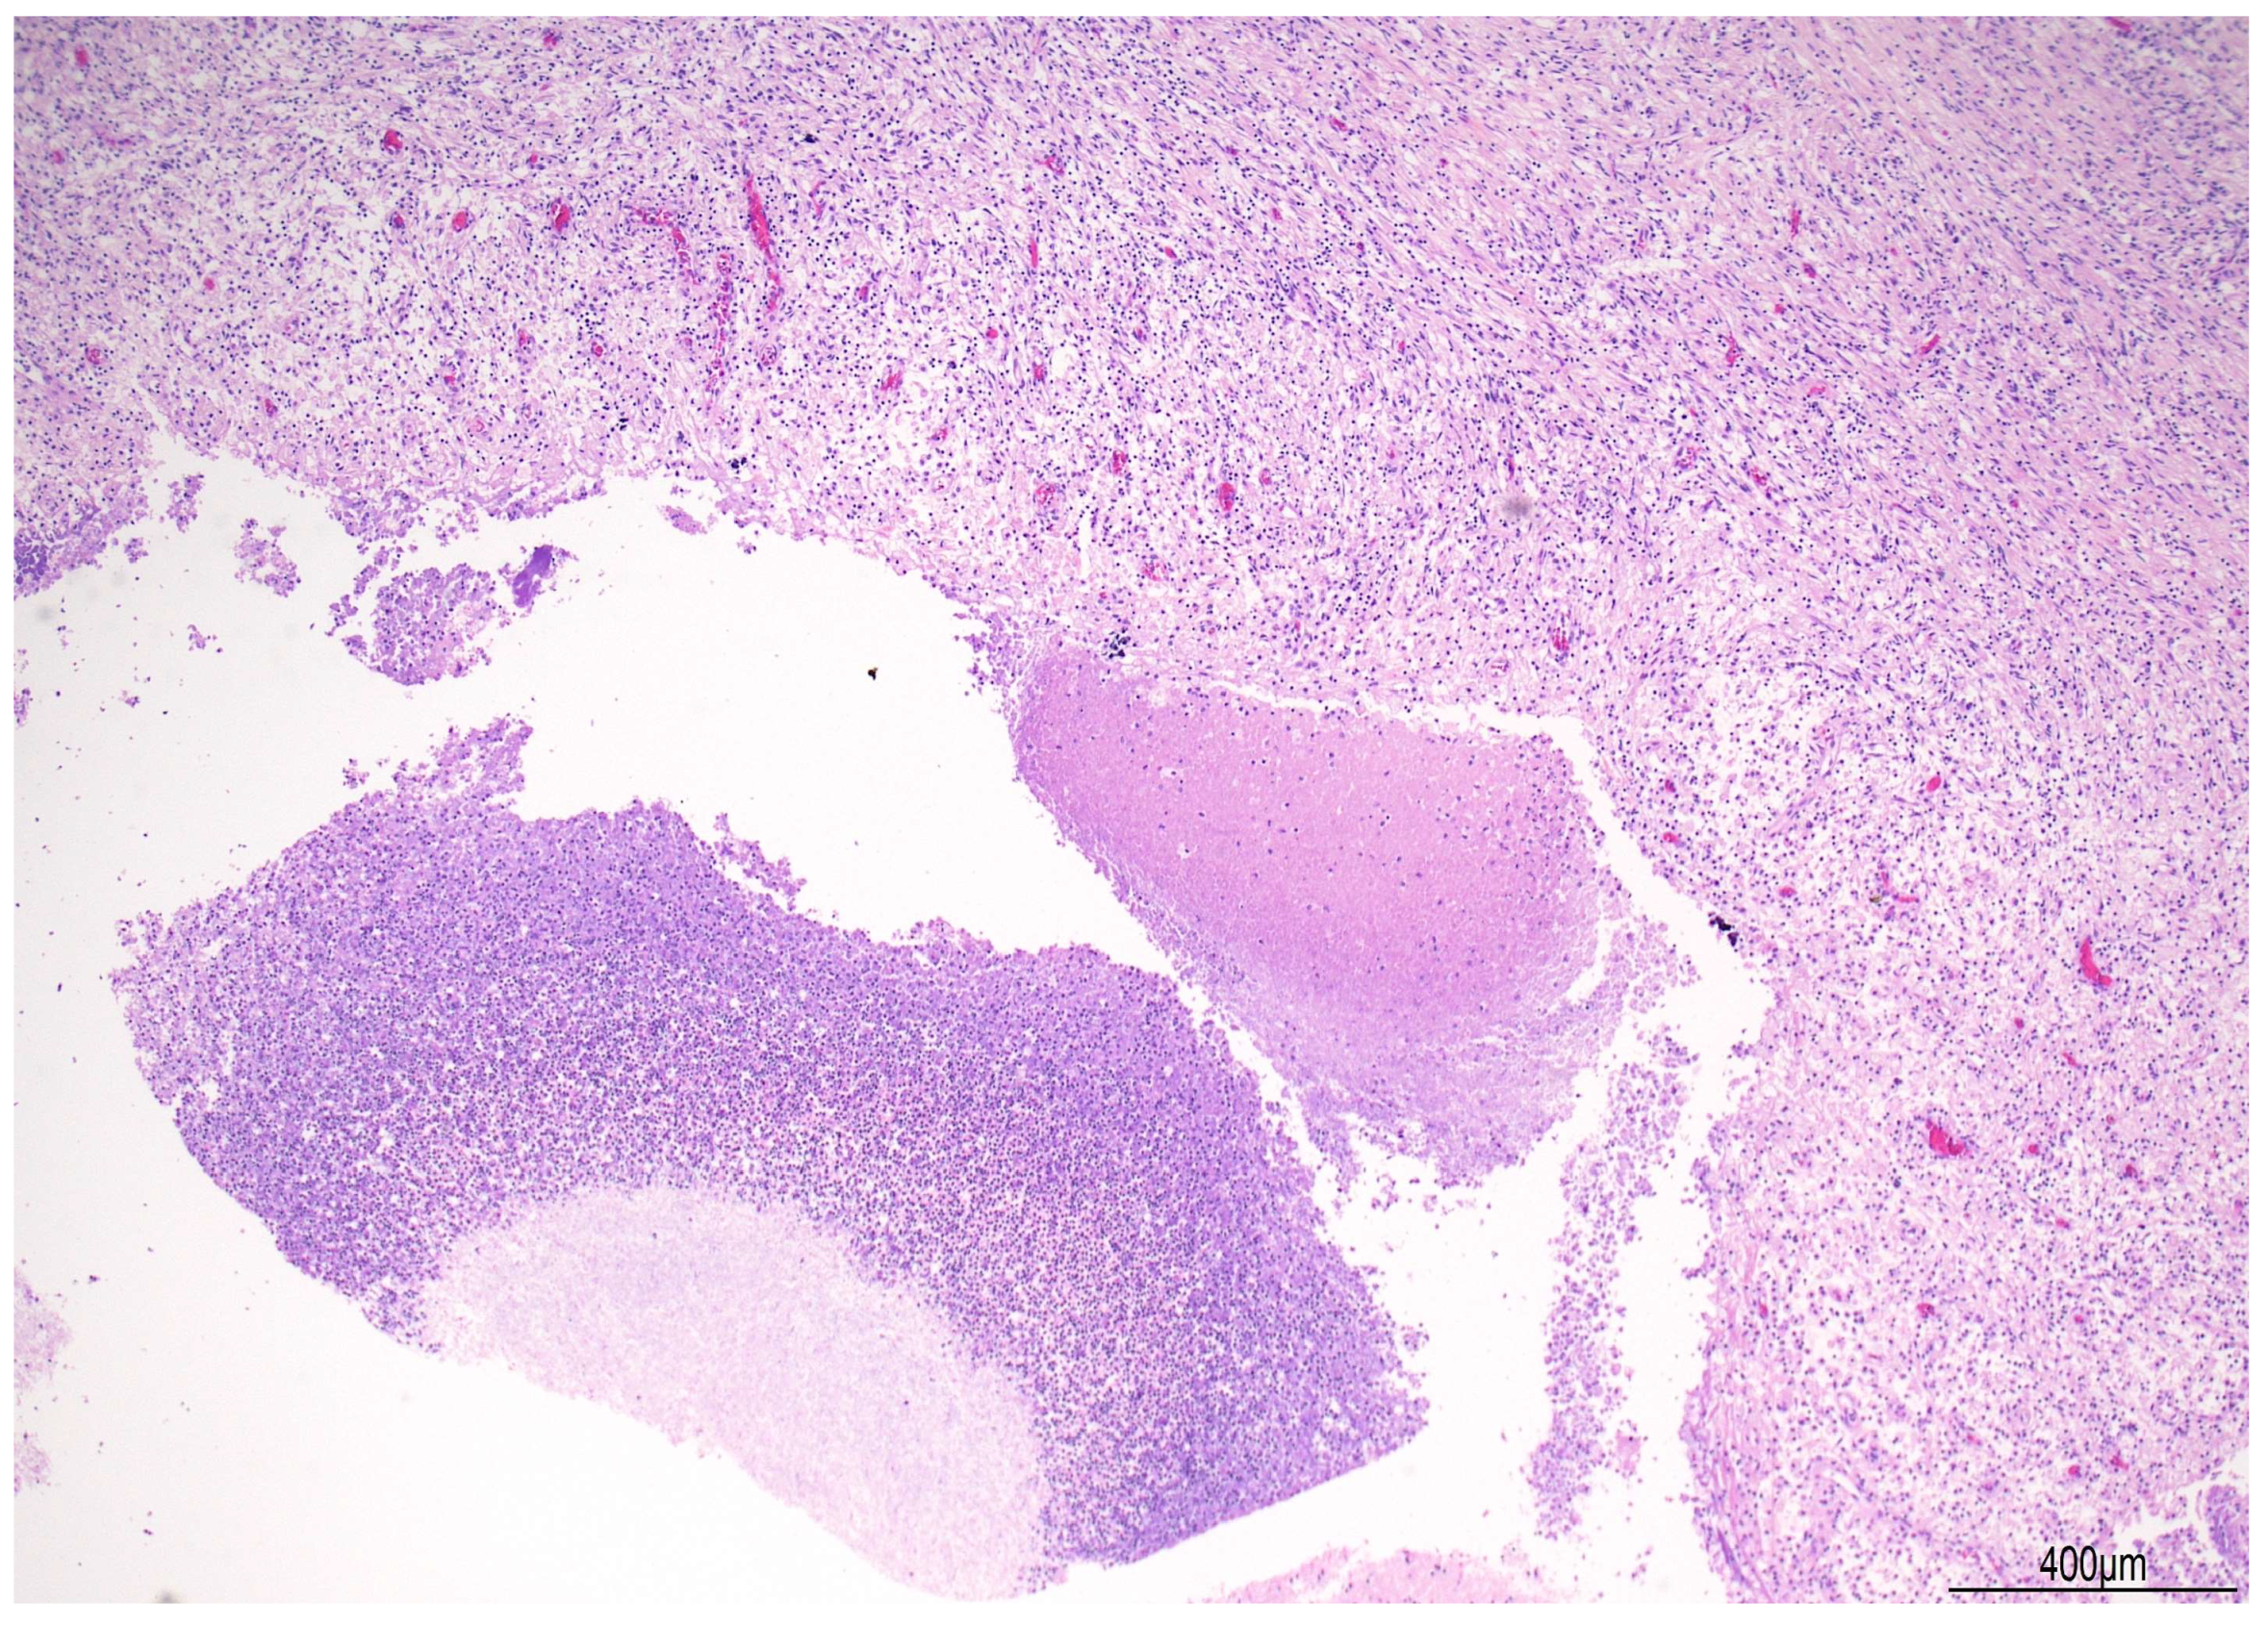

2.1. Autopsy Findings

| ~3 months after surgery | Progressive neurological decline, coma, death | Autopsy: PAS-D and GMS stains positive for fungal elements (Candida albicans) | – | Supportive intensive care until death |